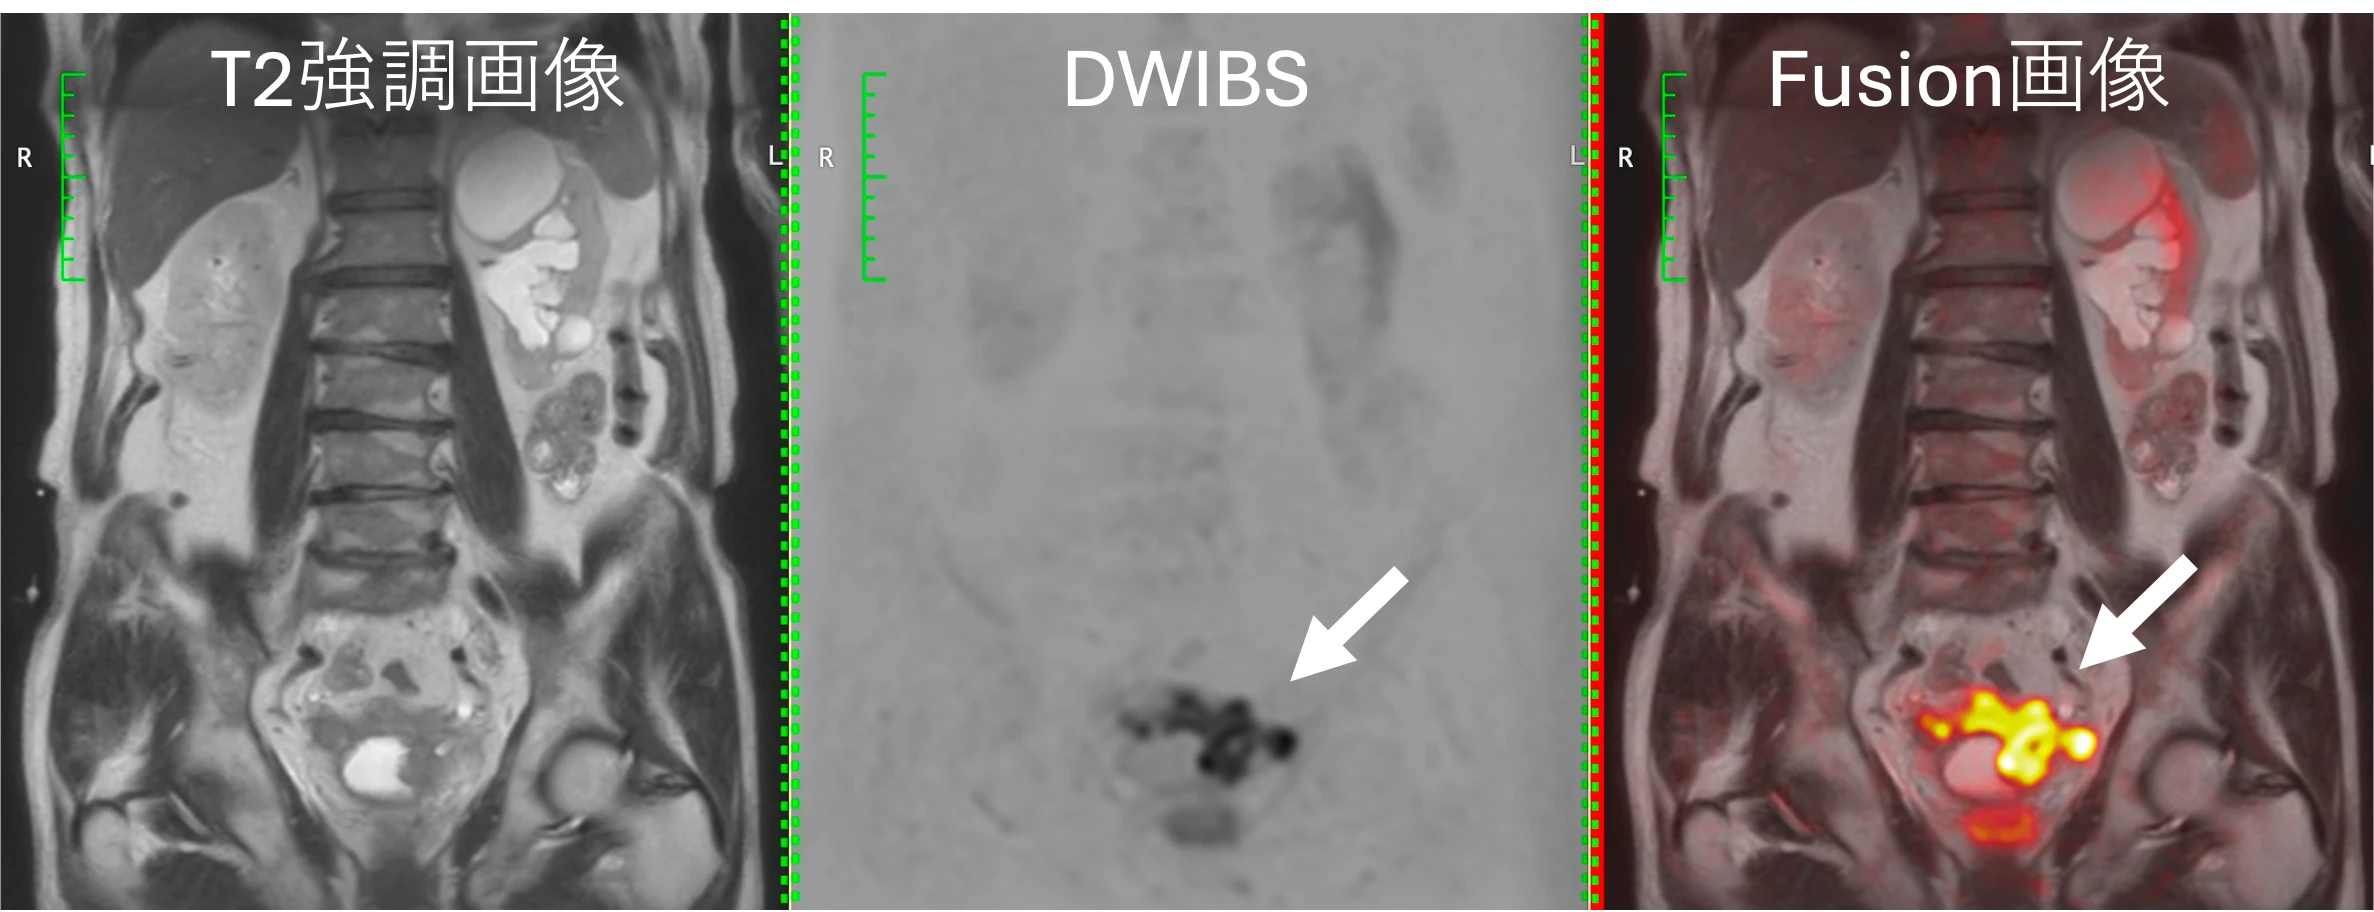

- 当クリニックでは、最近の研究の成果をいち早くお届けします。例えば、以下のように、さらにわかりやすい画像も作成します。

従来の全身MRIと、新しい表示(PET like MRI)

当クリニックの全身MRI検査は、すべてFusion画像が付帯します。病変と周囲臓器の位置関係がわかりやすくなり、正確性が増します。